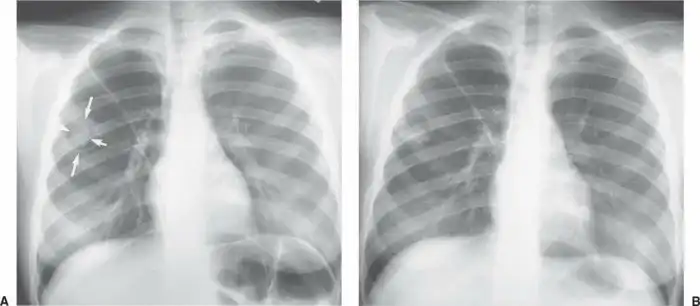

Рентгенограмма небольшой грибковой опухоли:

Женщина начинает готовиться к своим похоронам и искать место для операции, обзванивая платные раковые центры. Её навещают родные, близкие и друзья. Её поддерживают, и это здорово. Ей становится хуже с каждым днем. Хотя ничего, кроме КТ и рентгена, на рак не указывает. Её переводят в разные учреждения, пока медицинская комиссия вместе с врачом-диагностом не ставит под подозрение диагноз, основанный только на снимках. Посовещавшись в медицинских кругах, они начинают подозревать, что это может быть и не рак. Назначают новые анализы. В их числе анализ имунноглобулина Е к аспергиллезу. Полученный результат оказался настолько высоким, что был вне оценочной шкалы. У женщины обнаружили запущенный и разросшийся аллергический бронхолегочный аспергиллёз. Картина была настолько жуткой, что и КТ, и рентген в точности совпадали с характеристиками и внешним видом злокачественной опухоли, занимавшей почти всё легкое.

Рентгенограмма большой грибковой опухоли:

Бэтси в итоге спасли, и она успешно перешла от острой формы к хронической, оставшись на этом свете с кашлем, необходимостью постоянного лечения и жутковатым жизненным опытом. В её случае врачи пришли к мнению, что виновником заболевания стала компостная куча на заднем дворе, где у Бэтси был сад. Но так ли всё просто?

“Аспергиллез” лишь общее название весьма нескромной группы болезней, вызываемых грибами рода Aspergillus. В большинстве своем, заболевание наиболее характерно для уже больных или сильно ослабленных людей. Это все, кто перенес или всё ещё болеет самыми разными болезнями, связанными с легкими: от туберкулеза и хронической обструктивной болезни легких до астмы и тяжелых форм аллергий. В случае с Бэтси она обзавелась аспергилломой, проще говоря, в её легких разросся грибной мицелий. Чтобы в бронхе или в легком выросли грибы, недостаточно просто вдохнуть споры плесени. Вы и так это делаете постоянно. Для того, чтобы они прижились, необходимо иметь повреждения (в виде гранулемы, например). И тогда, попав в полость гранулемы, абсцесса или кисты, споры прорастают, и начинает расти аспергиллома.